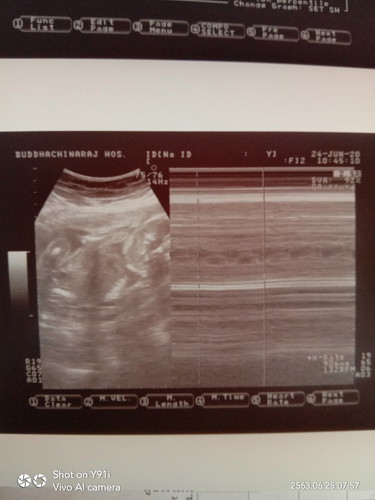

หมอนัดเจาะน้ำคล่ำมะวานเจ็บนิดหน่อย อยากเห็นหน้าเจ้าตัวน้อยแล้วล่ะ

ขอให้ผลออกมาปกตินะคะแม่